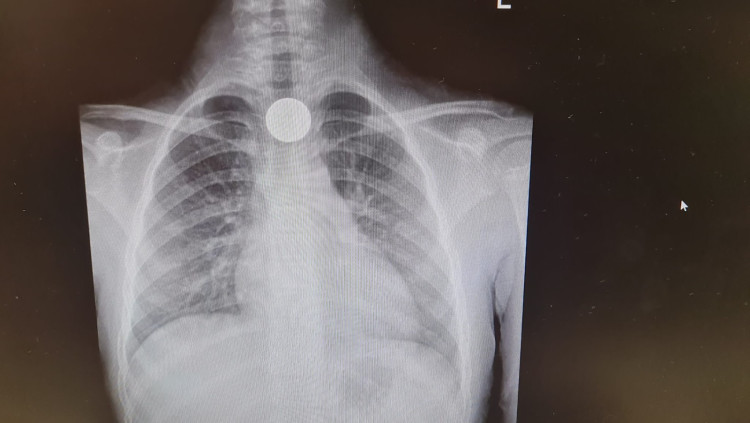

חשבה שזה בייגלה: ילדה בת שש וחצי מאשקלון בלעה מטבע והרופאים הצילו את חייה